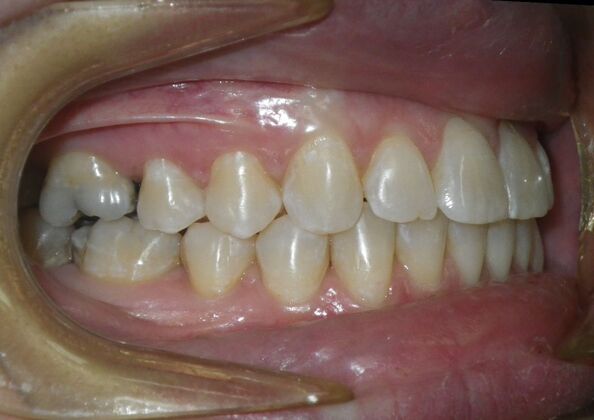

Invisalign: Case 18

This patient had concerns with the lower anterior teeth. There were some slight rotations and the midline of the lower incisors wasn't lined up with the upper midline. To correct this we used slenderizing of teeth in strategic areas of the lower arch to correct the rotations and line up the midlines. Patient very pleased with the results.